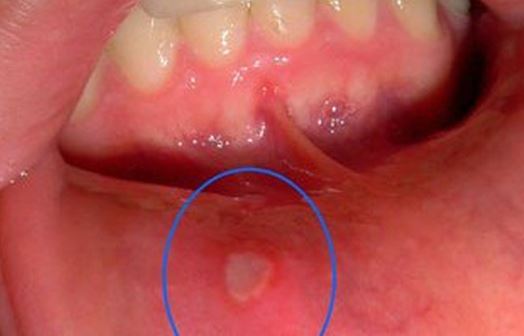

Nhiệt miệng là tình trạng khá phổ biến, gặp ở nhiều người và thường gây đau đớn, khó chịu, ảnh hưởng tới việc ăn uống. Dưới đây là 5 mẹo giúp bạn chữa nhiệt miệng nhanh chóng chỉ sau hai ngày mà không cần dùng đến thuốc.